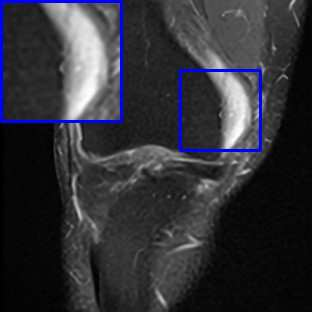

Limited by imaging systems, the reconstruction of Magnetic Resonance Imaging (MRI) images from partial measurement is essential to medical imaging research. Benefiting from the diverse and complementary information of multi-contrast MR images in different imaging modalities, multi-contrast Super-Resolution (SR) reconstruction is promising to yield SR images with higher quality. In the medical scenario, to fully visualize the lesion, radiologists are accustomed to zooming the MR images at arbitrary scales rather than using a fixed scale, as used by most MRI SR methods. In addition, existing multi-contrast MRI SR methods often require a fixed resolution for the reference image, which makes acquiring reference images difficult and imposes limitations on arbitrary scale SR tasks. To address these issues, we proposed an implicit neural representations based dual-arbitrary multi-contrast MRI super-resolution method, called Dual-ArbNet. First, we decouple the resolution of the target and reference images by a feature encoder, enabling the network to input target and reference images at arbitrary scales. Then, an implicit fusion decoder fuses the multi-contrast features and uses an Implicit Decoding Function~(IDF) to obtain the final MRI SR results. Furthermore, we introduce a curriculum learning strategy to train our network, which improves the generalization and performance of our Dual-ArbNet. Extensive experiments in two public MRI datasets demonstrate that our method outperforms state-of-the-art approaches under different scale factors and has great potential in clinical practice.